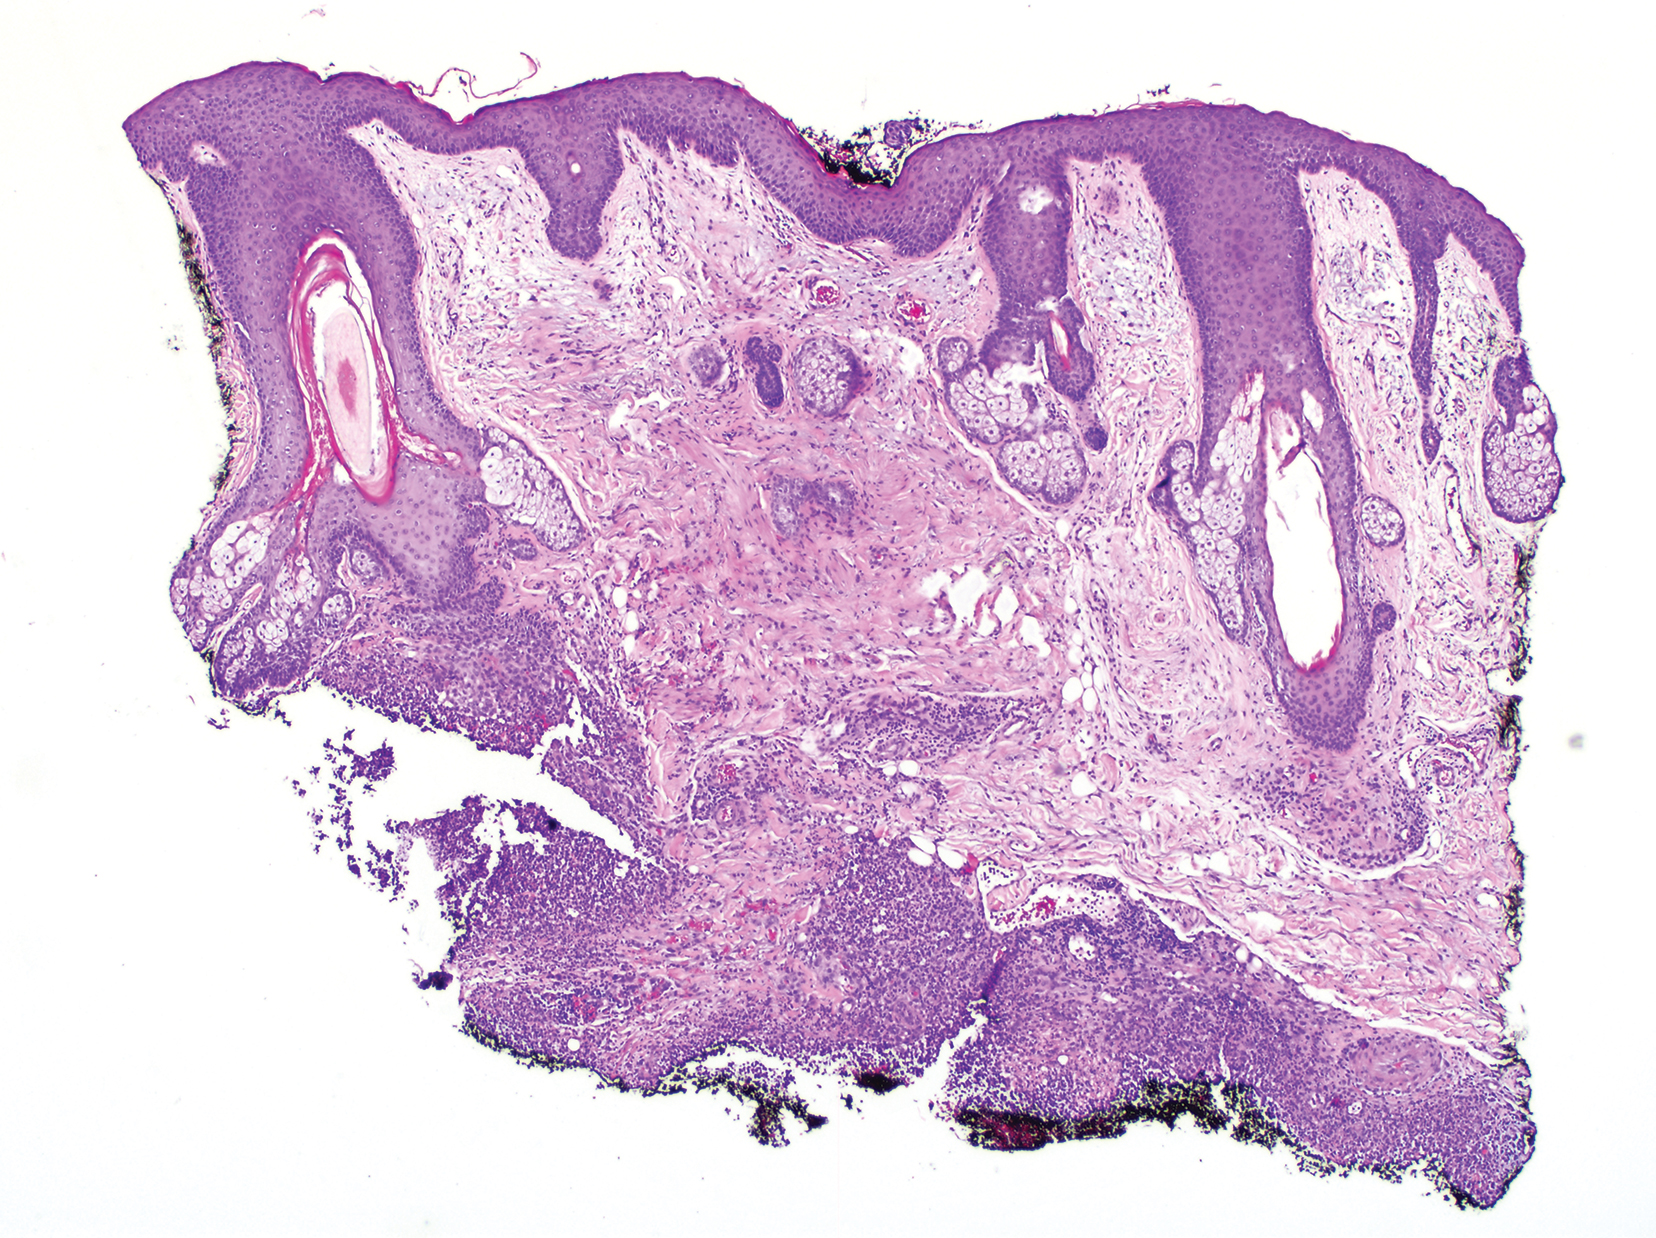

Clinically, the constellation of symptoms was thought to represent an infectious process or less likely metastatic malignancy. Biopsies of the nodule on the right side of the chin were performed and sent for culture and histologic examination. Sections from the anterior right chin showed compact orthokeratosis overlying a slightly spongiotic epidermis (Figure 3). Within the deep dermis, there was a dense mixed inflammatory infiltrate comprising predominantly neutrophils, with occasional eosinophils, lymphocytes, and histiocytes (Figure 4).

Figure 4. Histopathology revealed a mixed inflammatory infiltrate comprising predominantly neutrophils, with occasional eosinophils, lymphocytes, and histiocytes seen in the deep dermis (H&E, original magnification ×20)